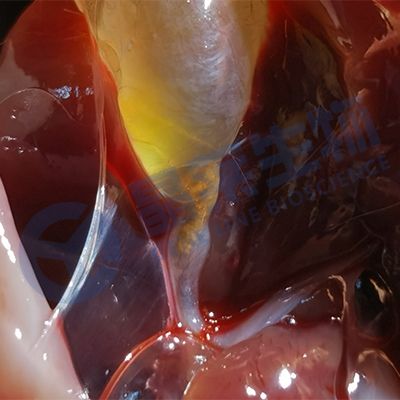

图中,胆囊的胆汁流出在吸墨纸上形成液面,A没有胆结石,B~F为大小不等、数量不等的胆结石。